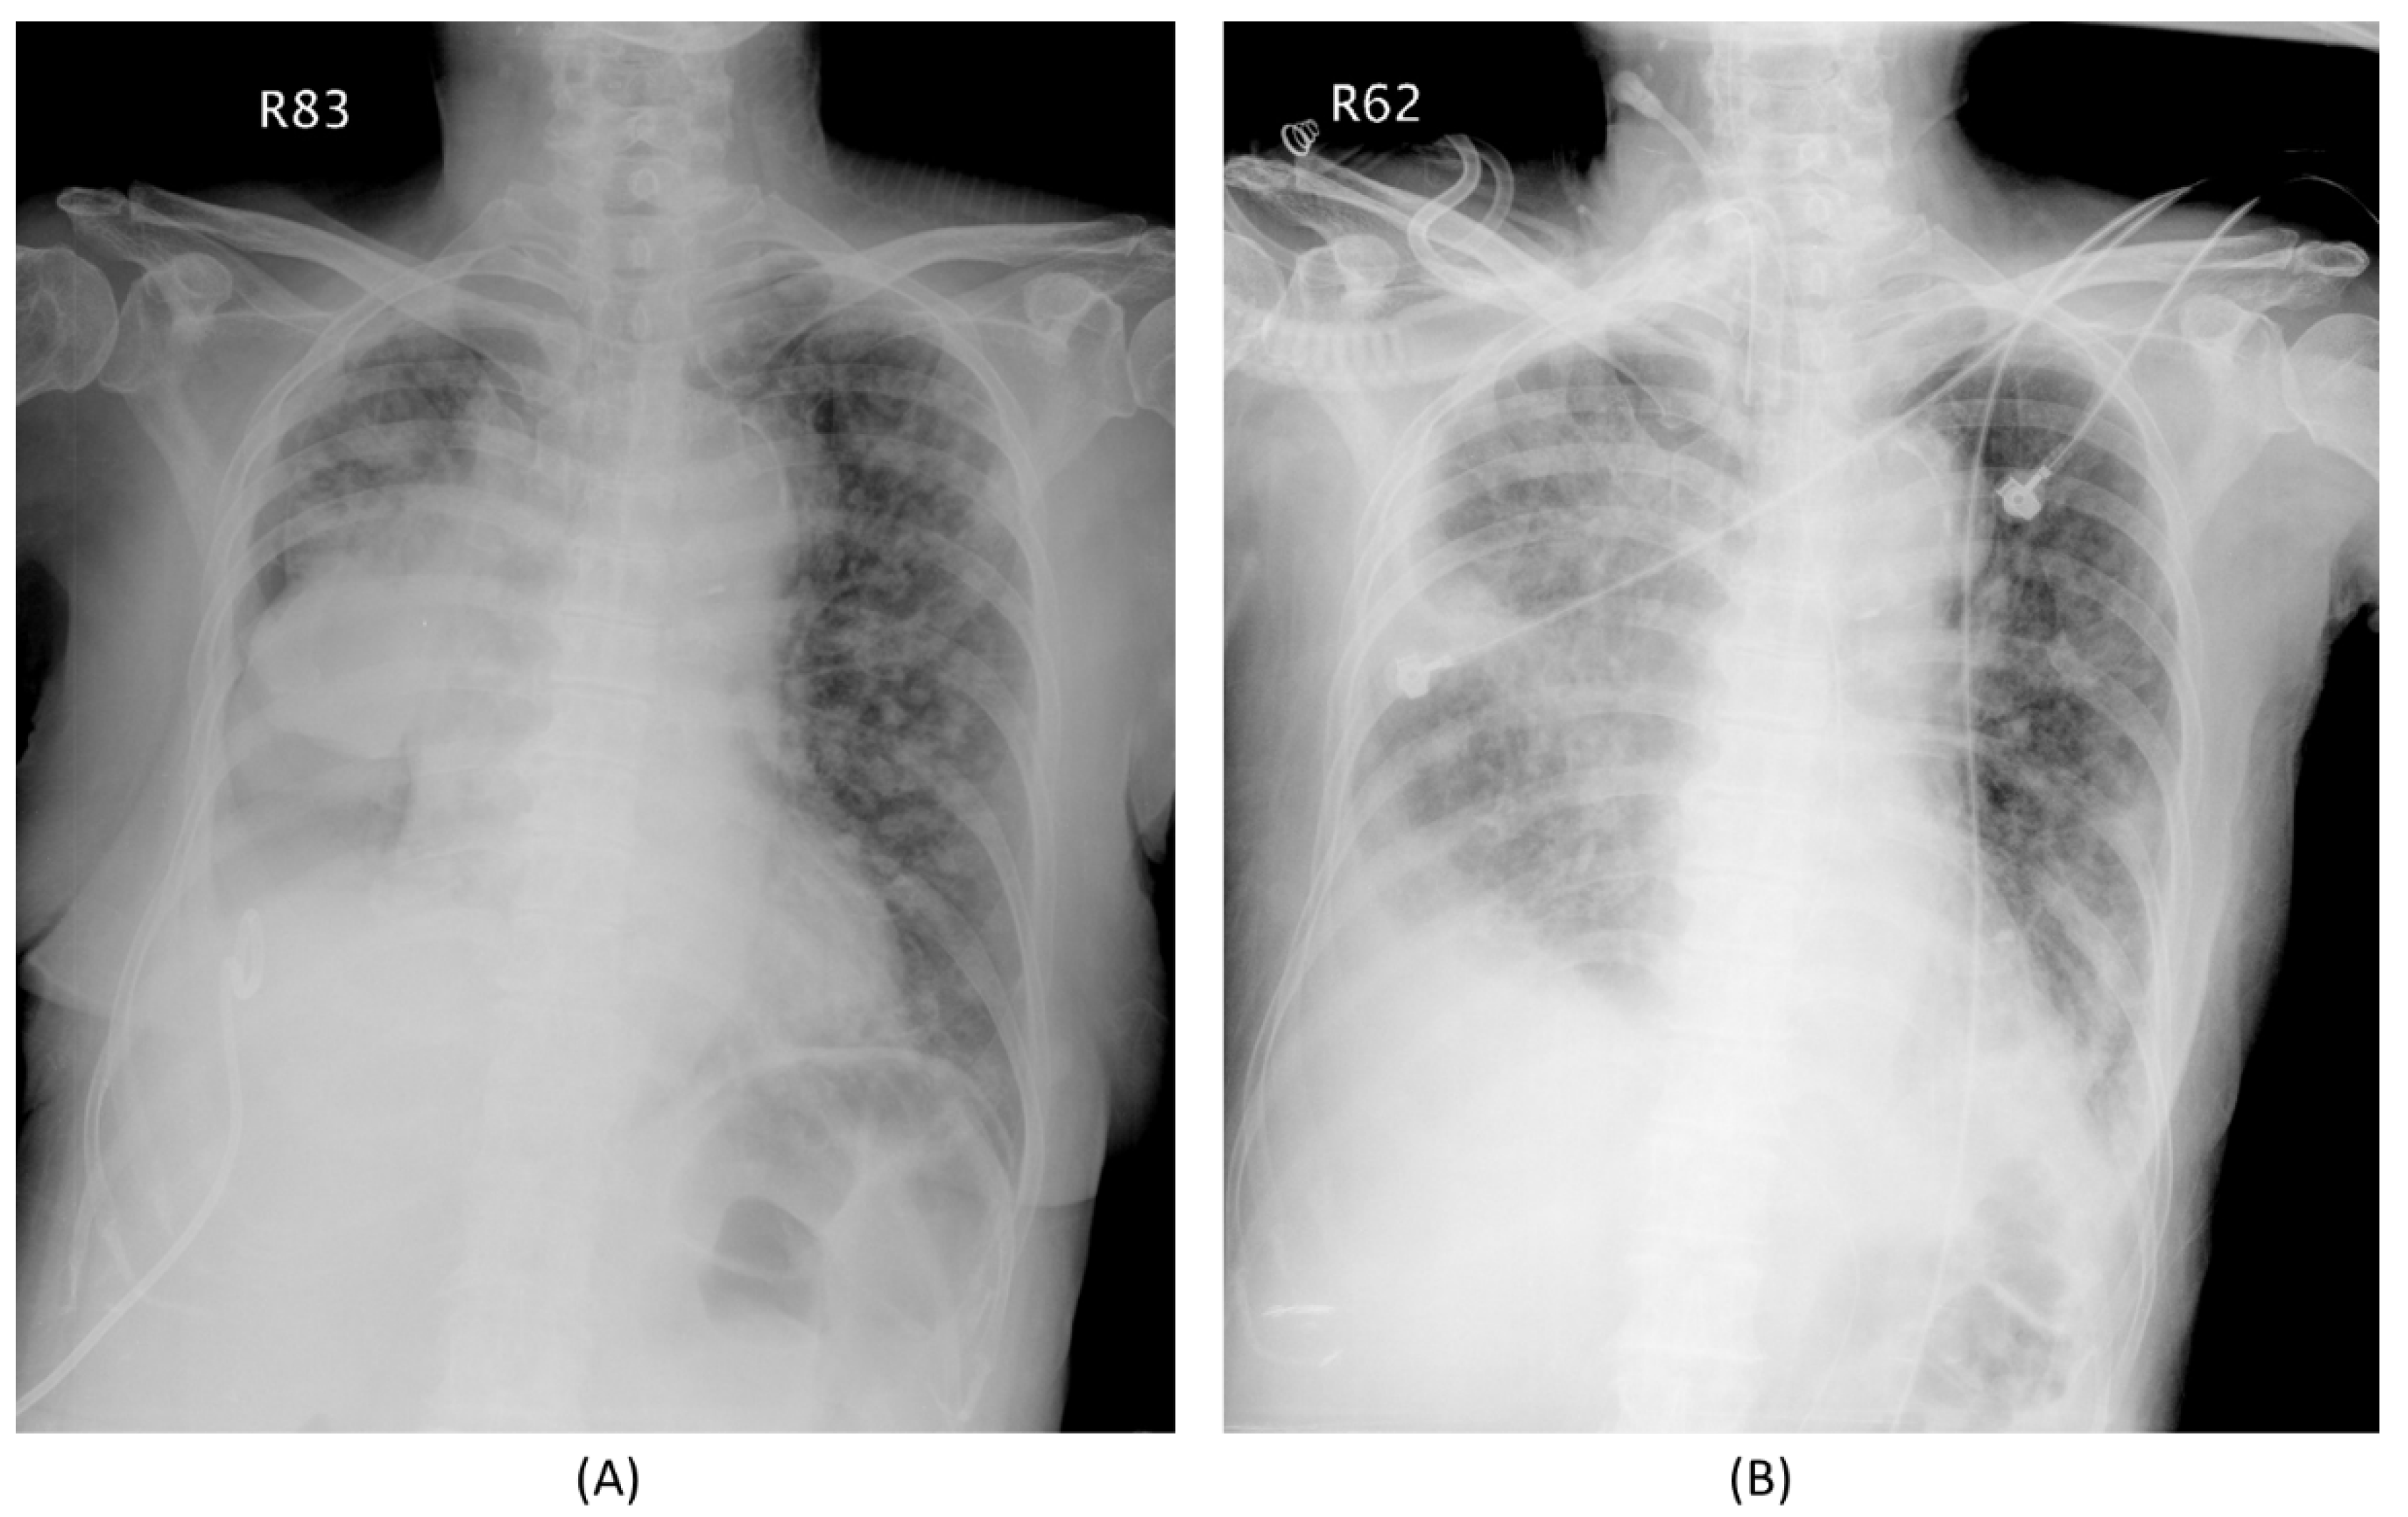

| CT image (n = 16) | ||

| CR/PR | 12 | 4 |

| SD/PD | 0 | 0 |

| Chest radiography (n = 19) | ||

| Improve | 3 | 0 |

| Stable/Deteriorate | 0 | 16 |